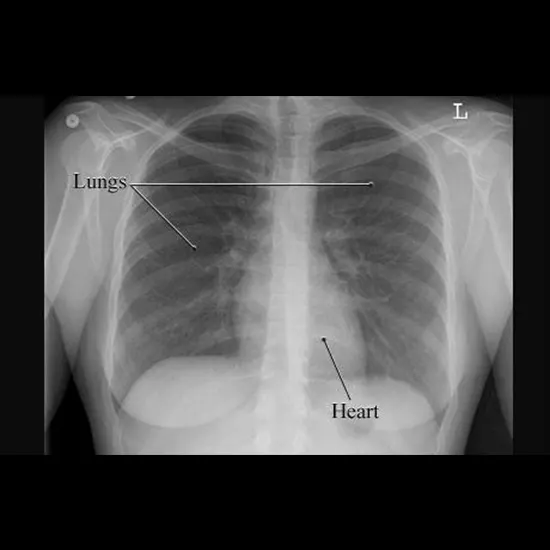

In respiratory health, X-rays are often used to consider the lungs, heart, and chest wall.

They can exhibit the measurement and structure of the lungs, the presence of fluid or air in the lungs or chest cavity, and the function of the coronary heart and different organs in the chest.